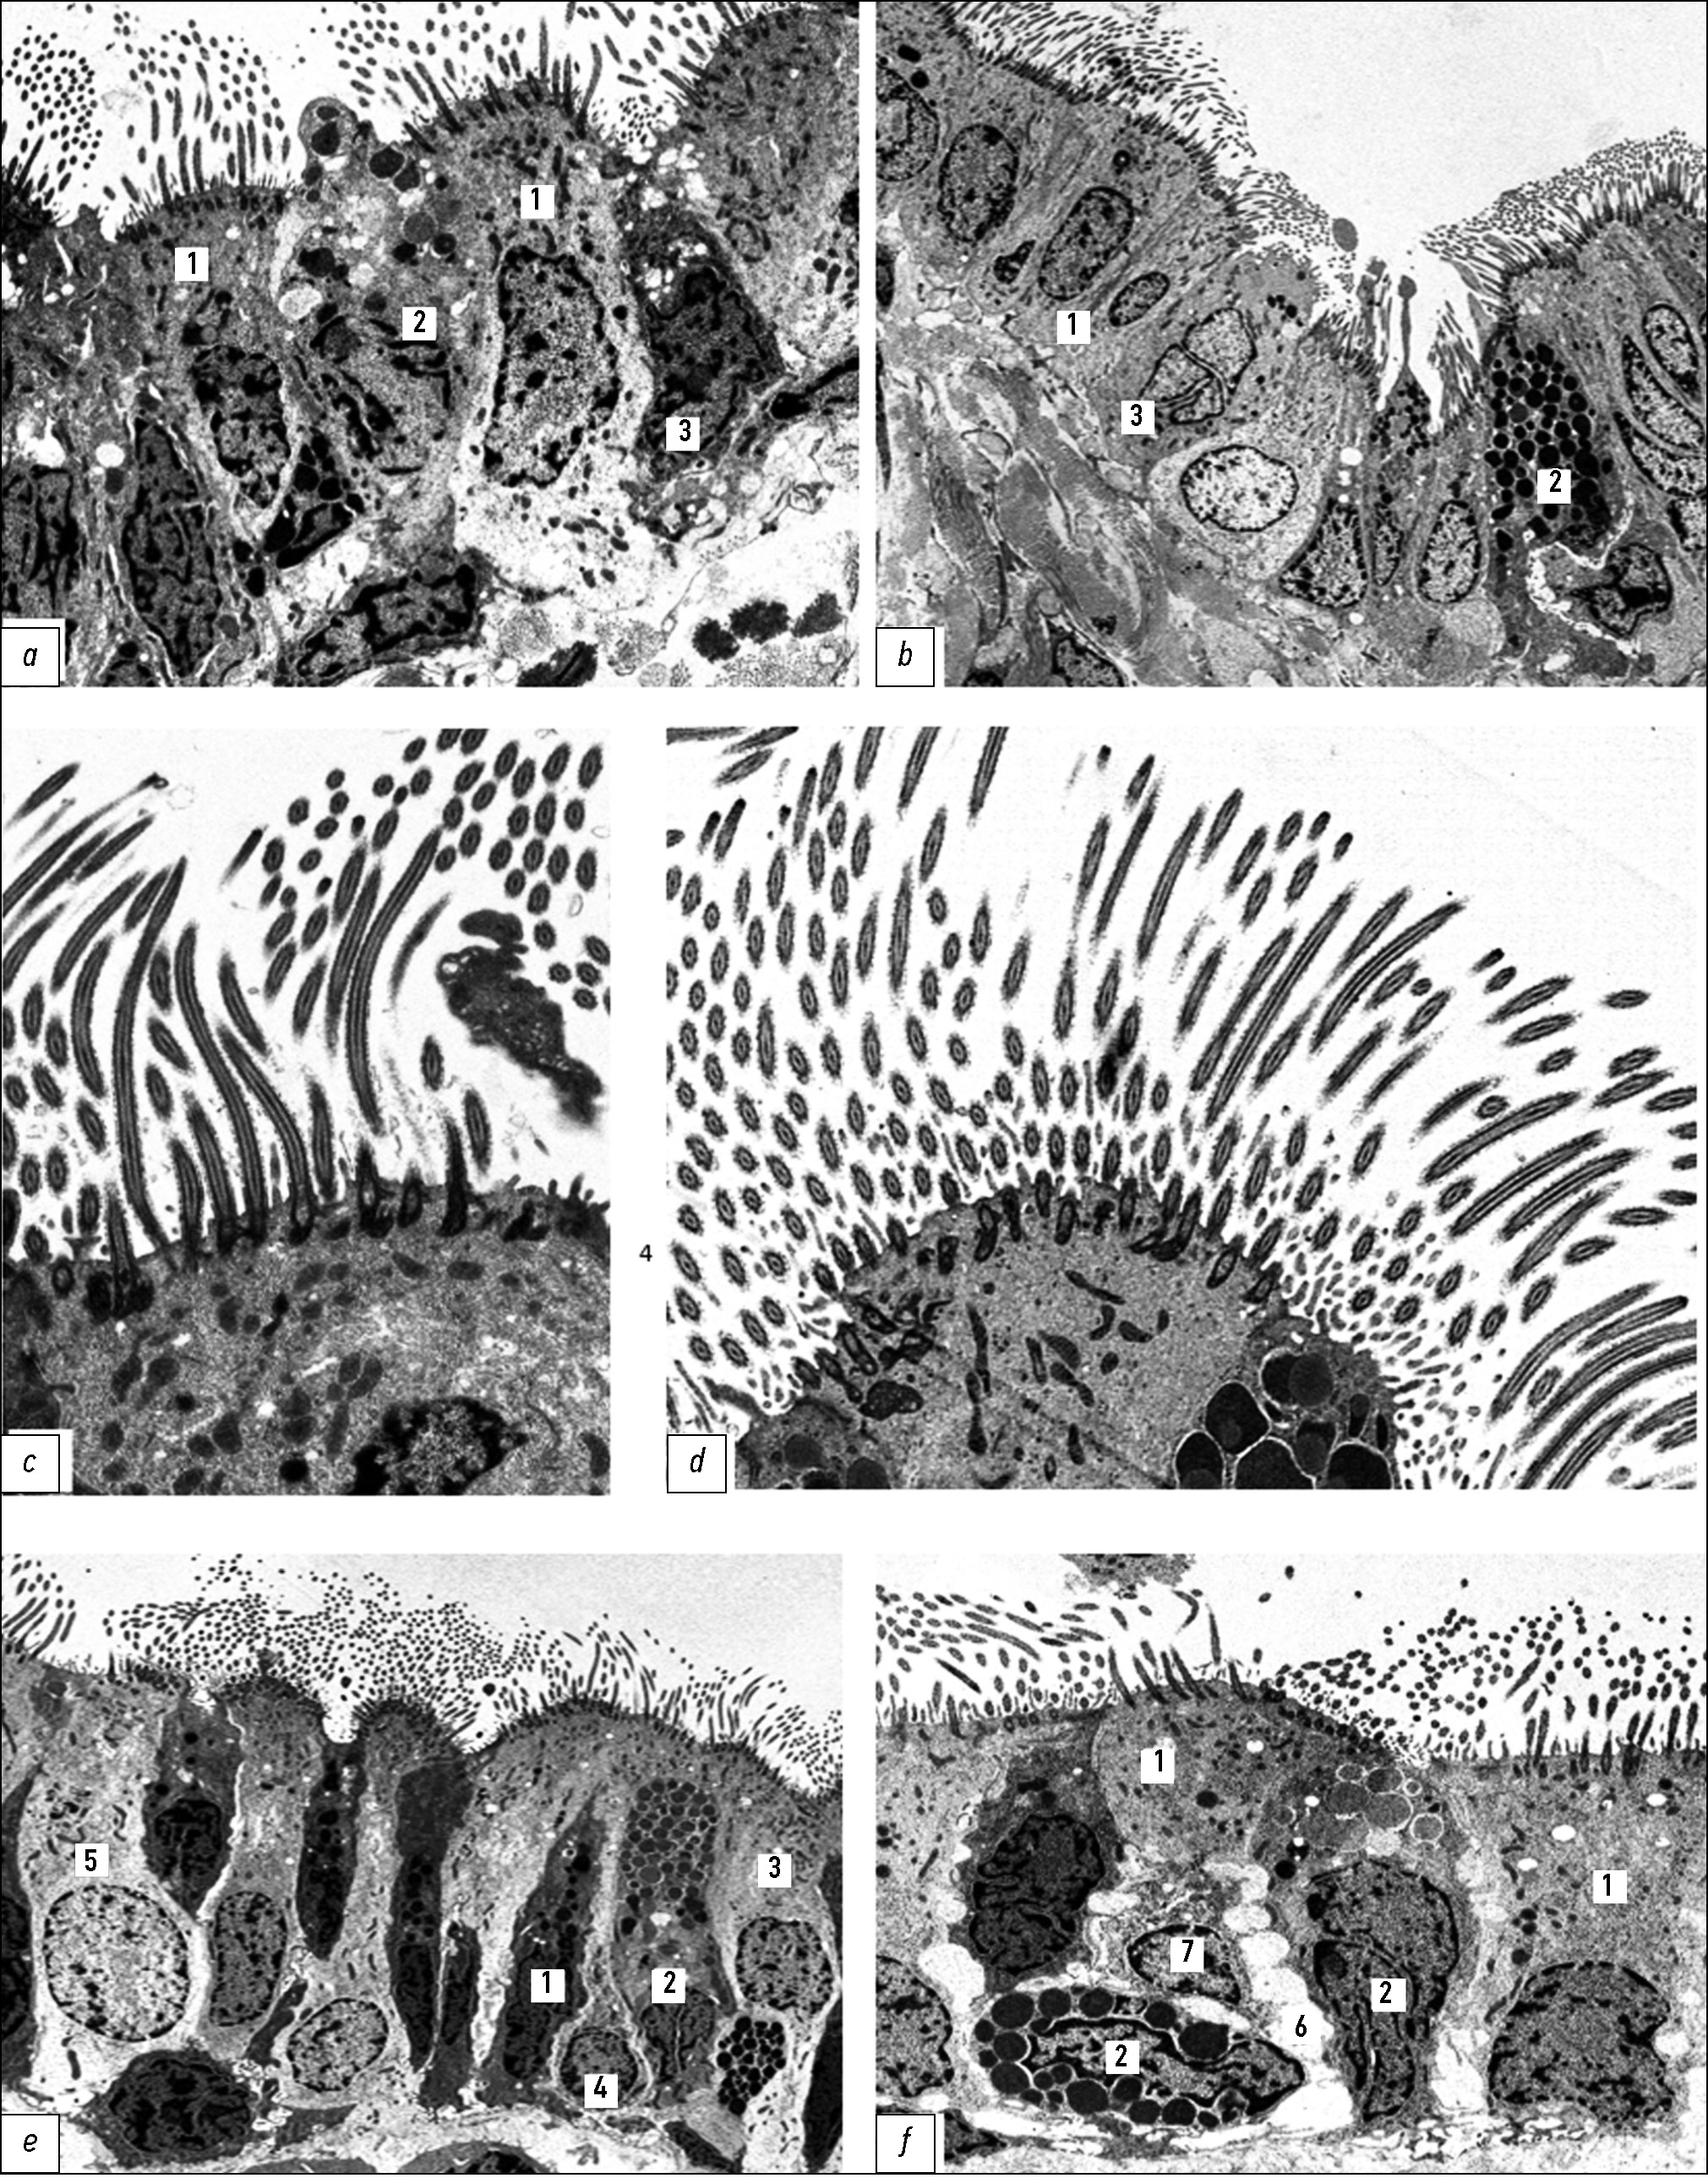

In newborn rats, the bronchial tree in all regions is lined with a simple epithelium composed predominantly of undifferentiated (intermediate) cells, whereas ciliated cells are relatively scarce (Fig. 1, a–c). During the first two weeks after birth, the proportion of ciliated cells in the epithelial layer increases markedly because of active differentiation processes (ciliogenesis), accompanied by a proportional decrease in the content of poorly differentiated elements. Various stages of ciliary formation can be observed at the apical poles of differentiating ciliated cells (Fig. 1, d, e). The maturation of ciliated cells occurs in clusters, which is clearly visible under scanning electron microscopy (Fig. 1, f). By the end of the first month after birth, the typical structure of a pseudostratified ciliated epithelium is established.

Fig. 1. Bronchial epithelial lining in rats: a, main bronchus; b, lobar bronchus; c–e, segmental bronchi in newborns; f, segmental bronchus in 8-day-old rats. 1, ciliated cells; 2, brush (non-ciliated) cells; 3, basal cells. Transmission electron microscopy: a–c, ×5000; d, e, ×8000; f, scanning electron microscopy, ×4500.